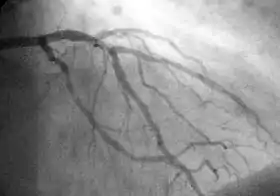

Coronary catheterization is one of the several cardiology diagnostic tests and procedures. Specifically, through the injection of a liquid radiocontrast agent and illumination with X-rays,[1] angiocardiography allows the recognition of occlusion, stenosis, restenosis, thrombosis or aneurysmal enlargement of the coronary artery lumens; heart chamber size; heart muscle contraction performance; and some aspects of heart valve function. Important internal heart and lung blood pressures, not measurable from outside the body, can be accurately measured during the test. The relevant problems that the test deals with most commonly occur as a result of advanced atherosclerosis – atheroma activity within the wall of the coronary arteries. Less frequently, valvular, heart muscle, or arrhythmia issues are the primary focus of the test.

If atheroma, or clots, are protruding into the lumen, producing narrowing, the narrowing may be seen instead as increased haziness within the X-ray shadow images of the blood/dye column within that portion of the artery; this is as compared to adjacent, presumed healthier, less stenotic areas.